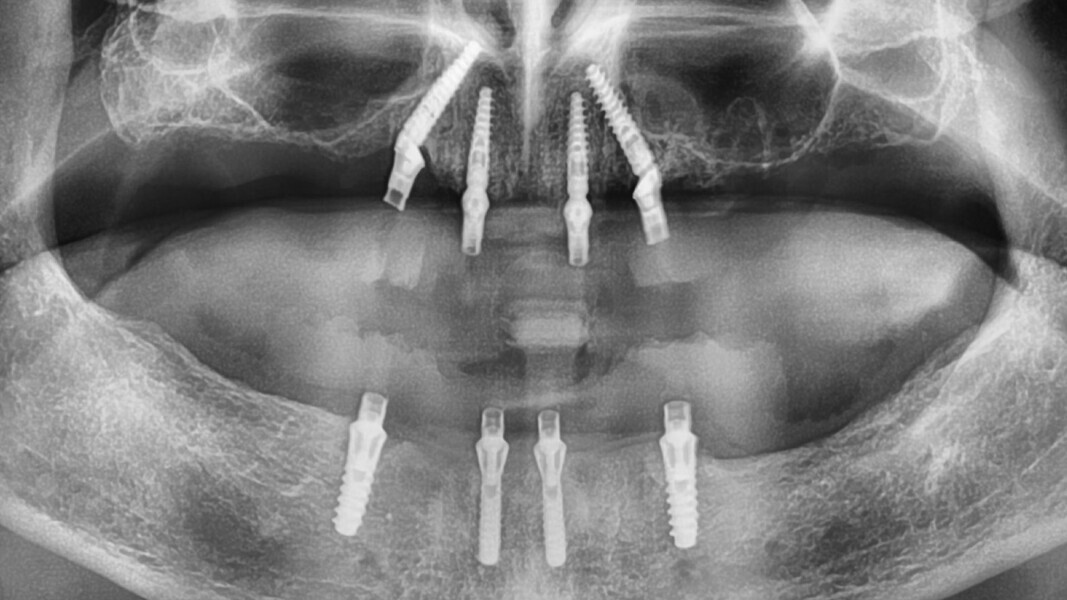

La radio panoramique (Fig. 15), quant à elle, nous montre une uniformité dans la répartition de la position des implants, ainsi qu’une connexion pilier conique-implant de type cône morse du All-on-4 au maxillaire, ce qui assure une étanchéité nécessaire à des implants posés en position infra-osseuse. Nous observons un cas classique de réhabilitation par quatre implants verticaux à la mandibule.